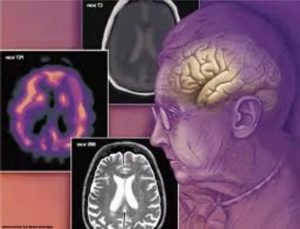

- КТ или МРТ головного мозга – изменения, выявляемые при помощи этих методов обследования, подтверждают не только наличие гидроцефалии, но и «объясняют» причину её формирования. То есть, помимо расширения желудочков, увеличения размера борозд и подпаутинного пространства, обнаруживается: блок ликворных путей объёмным образованием, поражение оболочек мозга и сосудистых сплетений в желудочках или визуализируются признаки нейродегенеративных заболеваний.

Гидроцефалия (водянка головного мозга) — избыточное накопление ликвора в желудочках мозга и подоболочечных пространствах; проявляется симптомами повышения ВЧД • Возникает вследствие дисбаланса между образованием и абсорбцией ликвора: абсорбируется меньше, чем образуется. Причиной может быть обструктивный процесс в желудочках либо в субарахноидальном пространстве, реже — истинная гиперпродукция ликвора (при папилломе ворсинчатого сплетения) • Характеризуется избыточным накоплением ликвора в желудочках мозга или субарахноидальном пространстве с их расширением • У новорождённых приводит к увеличению размеров черепа и атрофии головного мозга (снижение метаболизма в прилежащих участках головного мозга).